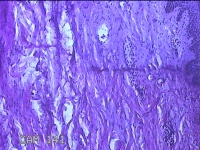

性别

男

年龄

50岁

临床诊断

皮脂腺囊肿

一般病史

发现左侧膝部包块8年余,无明显疼痛及不适。

标本名称

左侧膝部包块

大体所见

灰白暗红色组织3.3x2.3x0.8cm一块,表面带梭形皮肤3.5x1.5cm,皮下见包块3.3x1.5x0.8cm一个,切开包块呈实性,切面灰白粉红色,质软。

图3